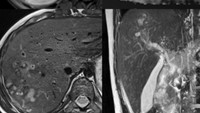

Meski cacing hati banyak ditemukan di hewan ternak, manusia juga bisa terjangkit. Ini adalah contoh rontgen anak 9 tahun di Azerbaijan yang mengalami pembengkakan hati akibat infeksi cacing. (Foto: Instagram/russian.radiology)